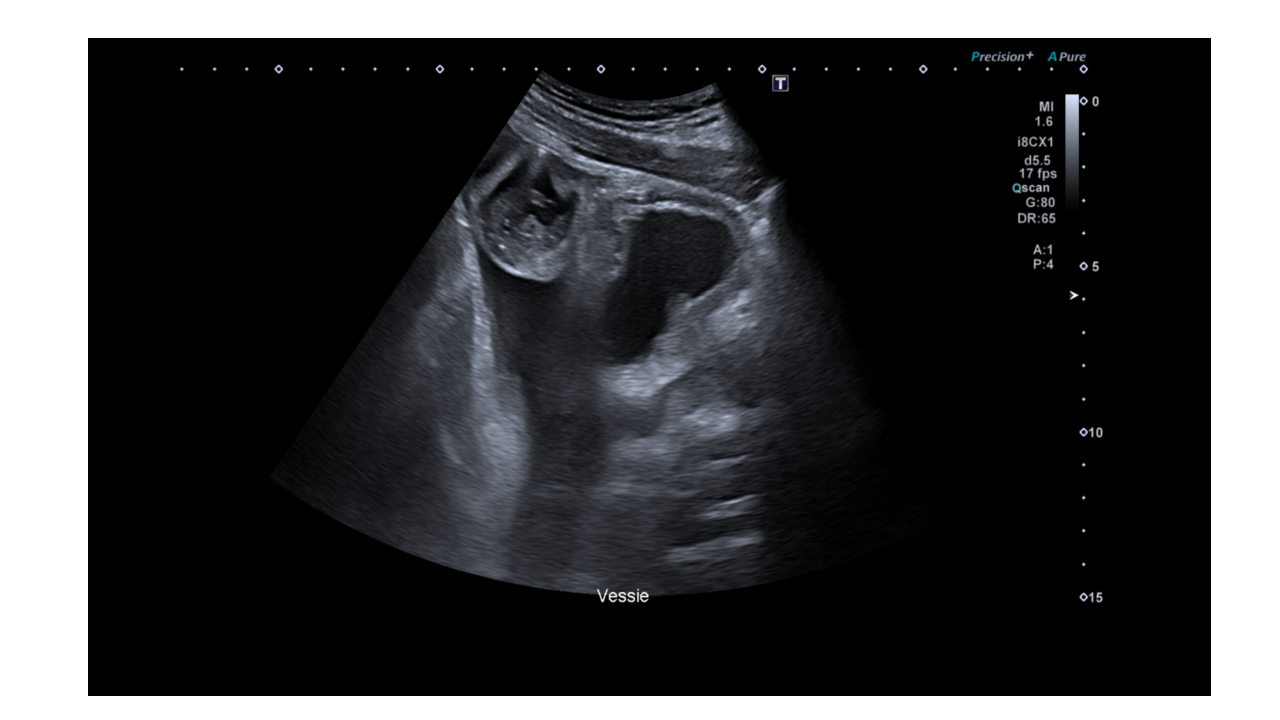

Apres avoir exploré les reins, la prostate (en sus pubien) et la vessie, son attention se porte sur cette image, à droite de la vessie sur une coupe sagittale, et sur l'ascite dans le cul de sac de douglas.

Le patient présente des douleurs abdominales, un balayage complémentaire est alors réalisé avec une fréquence d’émission augmentée pour mettre en évidence cette structure.

Une distension d'une anse grêle mesurée à 37mm de diamètre antéro postérieur est détectée.

Le diamètre d’une anse grêle ne doit pas dépasser 25mm .

Un apéristaltisme est ausi observé.